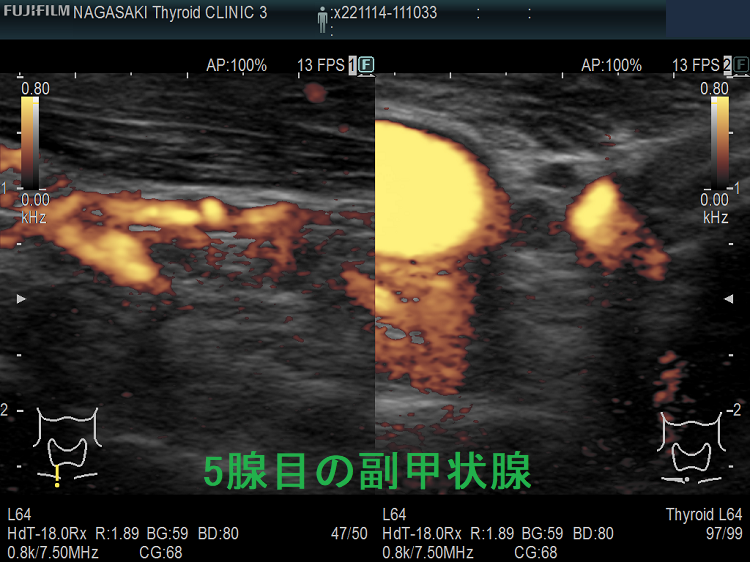

高カルシウム血症の程度と副甲状腺腫の大きさは必ずしも比例しない